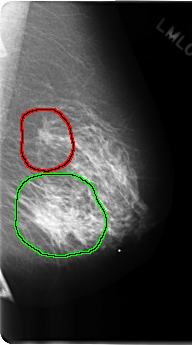

C_0191_1.LEFT_MLO

FILE: C_0191_1.LEFT_MLO.OVERLAY

TOTAL_ABNORMALITIES 2

ABNORMALITY 1

LESION_TYPE MASS SHAPE IRREGULAR MARGINS SPICULATED

ASSESSMENT 5

SUBTLETY 5

PATHOLOGY MALIGNANT

TOTAL_OUTLINES 1

BOUNDARY

ABNORMALITY 2

LESION_TYPE MASS SHAPE IRREGULAR MARGINS ILL_DEFINED